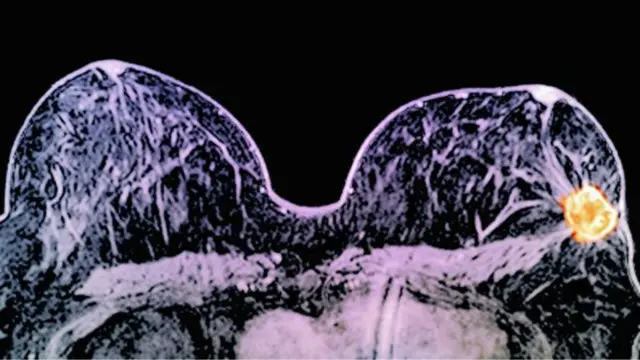

په "۱۱ ورځو" کې د سينې سرطان ناروغۍ درملنه

بريتانوي ډاکتران وايي د دوو ځانګړو درملو د کارولو نتيجه کې يې په ۱۱ وروځو کې د سينې سرطان درملنه کړې ده.

د ډاکترانو په وينا د دغو تجربو لپاره د "ليپاټينب" او "ټرسټوزماب" درمل چې په "هرسېپټين" مشهور دي کارول شوي دي.

دغه دواړه درمل په ښځو کې د سينې سرطان هغه حجرې په نښه کوي چې د دغې ناروغۍ په خپرېدو کې مرسته کوي.